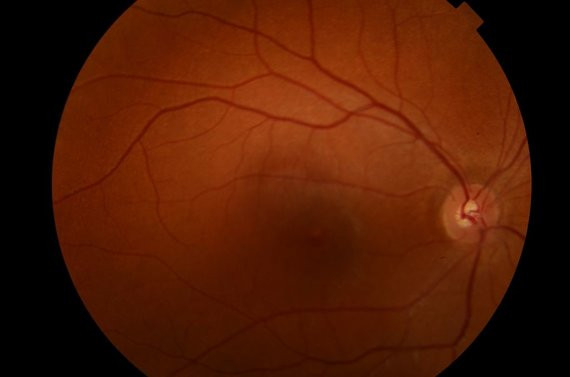

Glaukoma – klastingiausia akių liga

Pati klastingiausia akių liga yra glaukoma. Tai netgi ištisa akių ligų grupė, o jos padariniai – regos nervo atrofija ir negrįžtamas regos praradimas. Gydytojas paaiškina, kad susirgus glaukoma žūsta regos nervo skaidulos – dėl to siaurėja žmogaus regos laukas. Kadangi pradedama prasčiau matyti iš šonų, žmonės, sergantys glaukoma, neretai per vėlai apie tai sužino. Taip pat pasitaiko atvejų, kad žmogus viena akimi beveik visiškai apanka, tačiau matydamas kita, to nepastebi. „Kartais žmogus užkliūna už staktos ar kėdės, tačiau neatkreipia dėmesio, kad tiesiog nebemato objektų, kurie yra šoniniame vaizde. Jam nieko neskauda, o akis lėtai gęsta.

Ar galima tai išgydyti? Ne. Tačiau padėti galima – jei žmogus gydosi ir prisižiūri, dažniausiai jam užteks regėjimo iki gyvenimo galo“, – sako A. Makselis. Glaukoma pradedama gydyti lašais. Tačiau gydant šią ligą dažnai į akis lašinami vaistai iš kelių buteliukų. Tai ir yra didžiausia bėda – pavyzdingai gydymo plano laikosi ir vaistų nesupainioja tik apie ketvirtadalis pacientų. Jei nepadeda medikamentinis gydymas, glaukomą taip pat galima gydyti operacija.